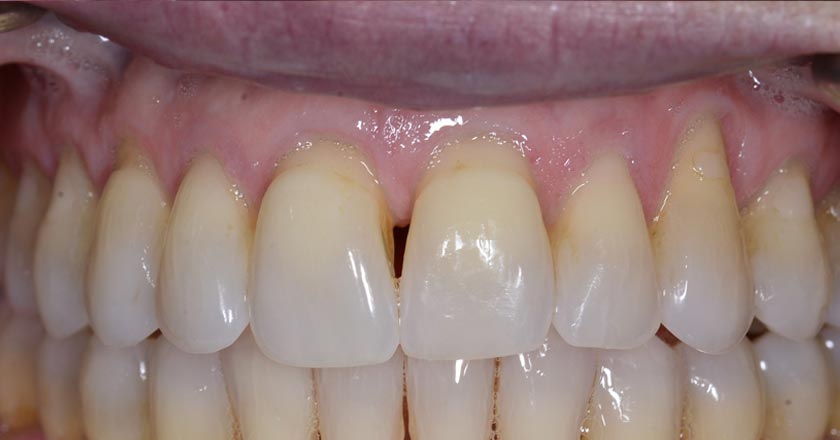

Implant - Before And After